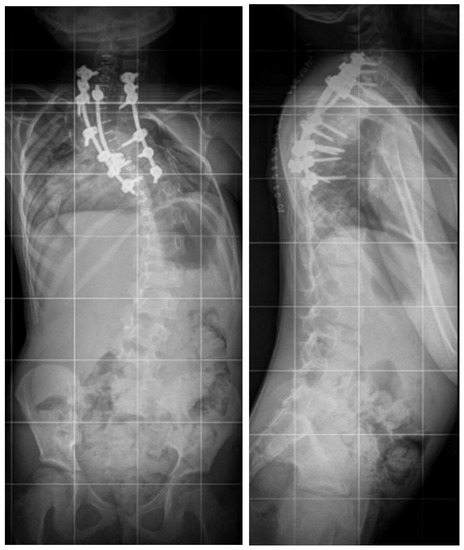

Correction of the deformity included right-sided compression and left-sided distraction. The pleura remained intact during the surgery, and no chest tube was needed (Figure 6).

Figure 6. Standing X-rays of the five-year-old girl after surgical treatment via the posterior approach and VCR T3–T4.